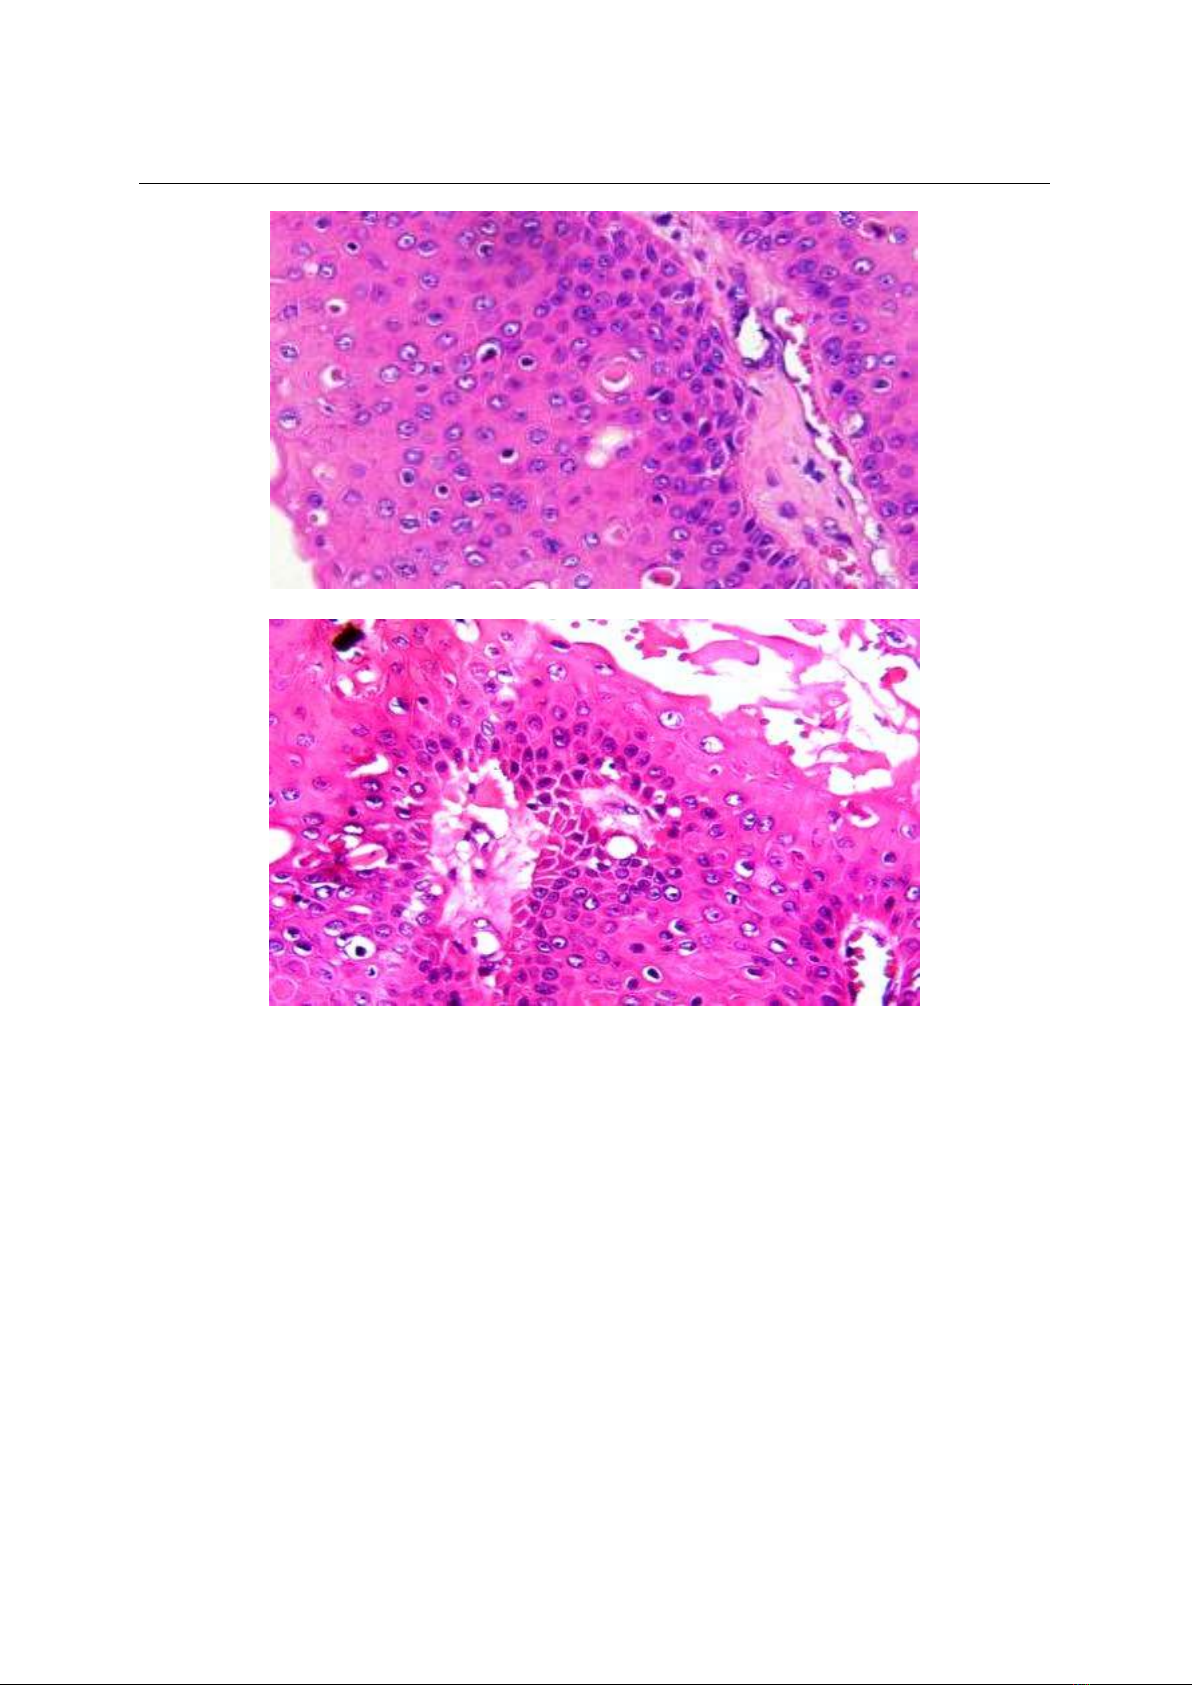

Bệnh nhn được tiểu phẫu, lấy u làm Giải

phẫu bệnh: U mật đ chắc, kch thưc 1,5 x

2cm, ranh gii rõ, mt cắt không đồng nhất,

nâu xám. Chẩn đoán ban đầu nghĩ đến trường

hợp SCC biệt hóa tốt. Kết hợp lm sàng, đánh

giá lại vi thể cho thấy u thể hiện hình ảnh: các

tế bào gai quá sản mạnh, co cụm thành ổ hoc

thùy, các tế bào dạng cận đáy sắp xếp xung

quanh, trưng thành về trung tâm thùy, có hình

ảnh sừng ha nang lông, màng đáy còn nguyên

vẹn có ít nhân chia vùng thấp tế bào, lan tỏa

trong lp chn bì su, mô đệm phù nề xơ ha,

ít tế bào viêm xâm nhiễm. (Hình 3, 4, 5, 6,

7&8).

Hình 3: Tiêu bản H23-4844 x4.H&E

Hình 4: Tiêu bản H23-4844 x10.H&E

Hình 5: Tiêu bản H23-4844 x10.H&E